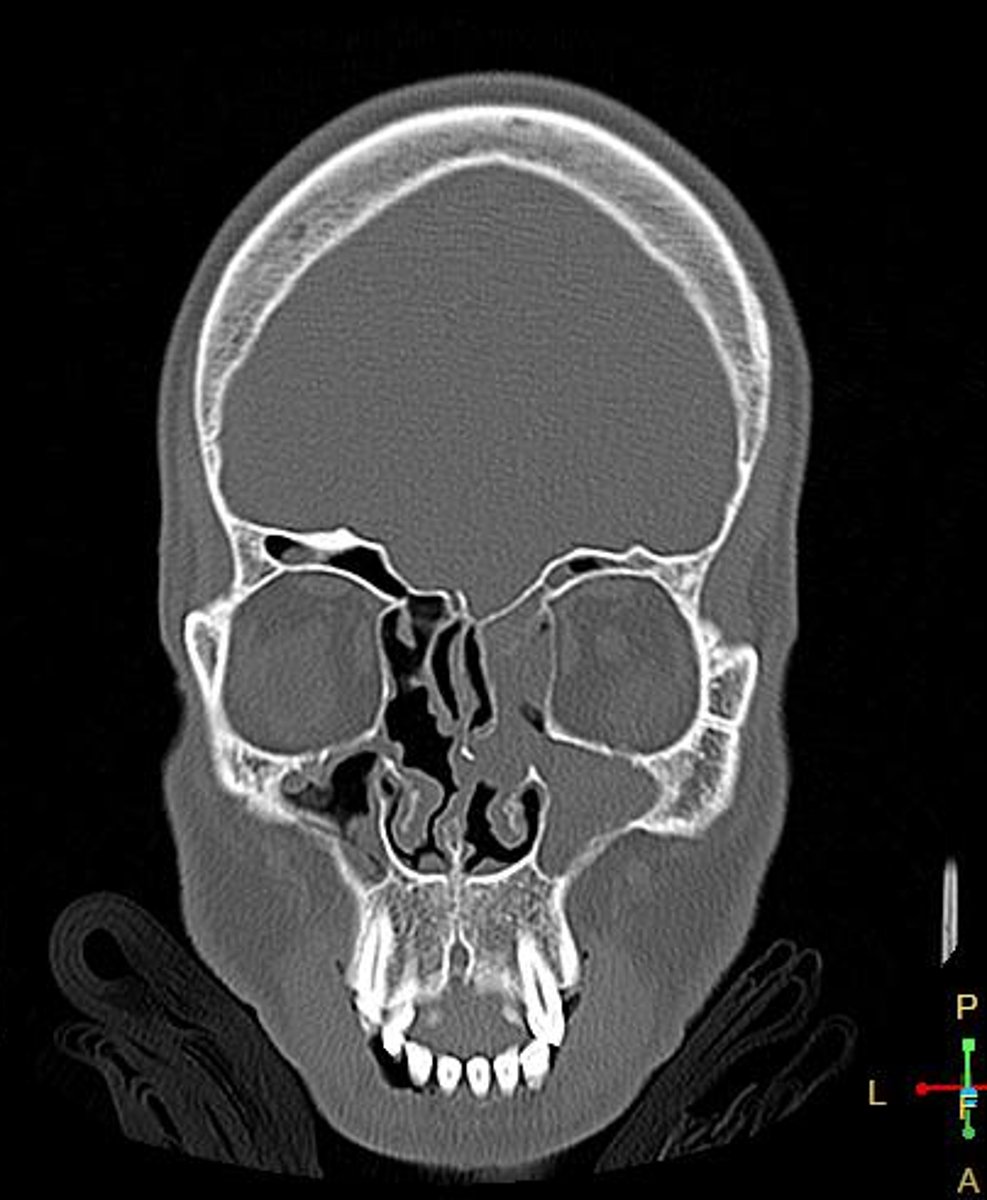

Paranasal sinus

What is the location of the lesion?

Osteoma

Most likely diagnosis?

Headaches

Concerns/complications?

Refer to EENT

What is your next step?